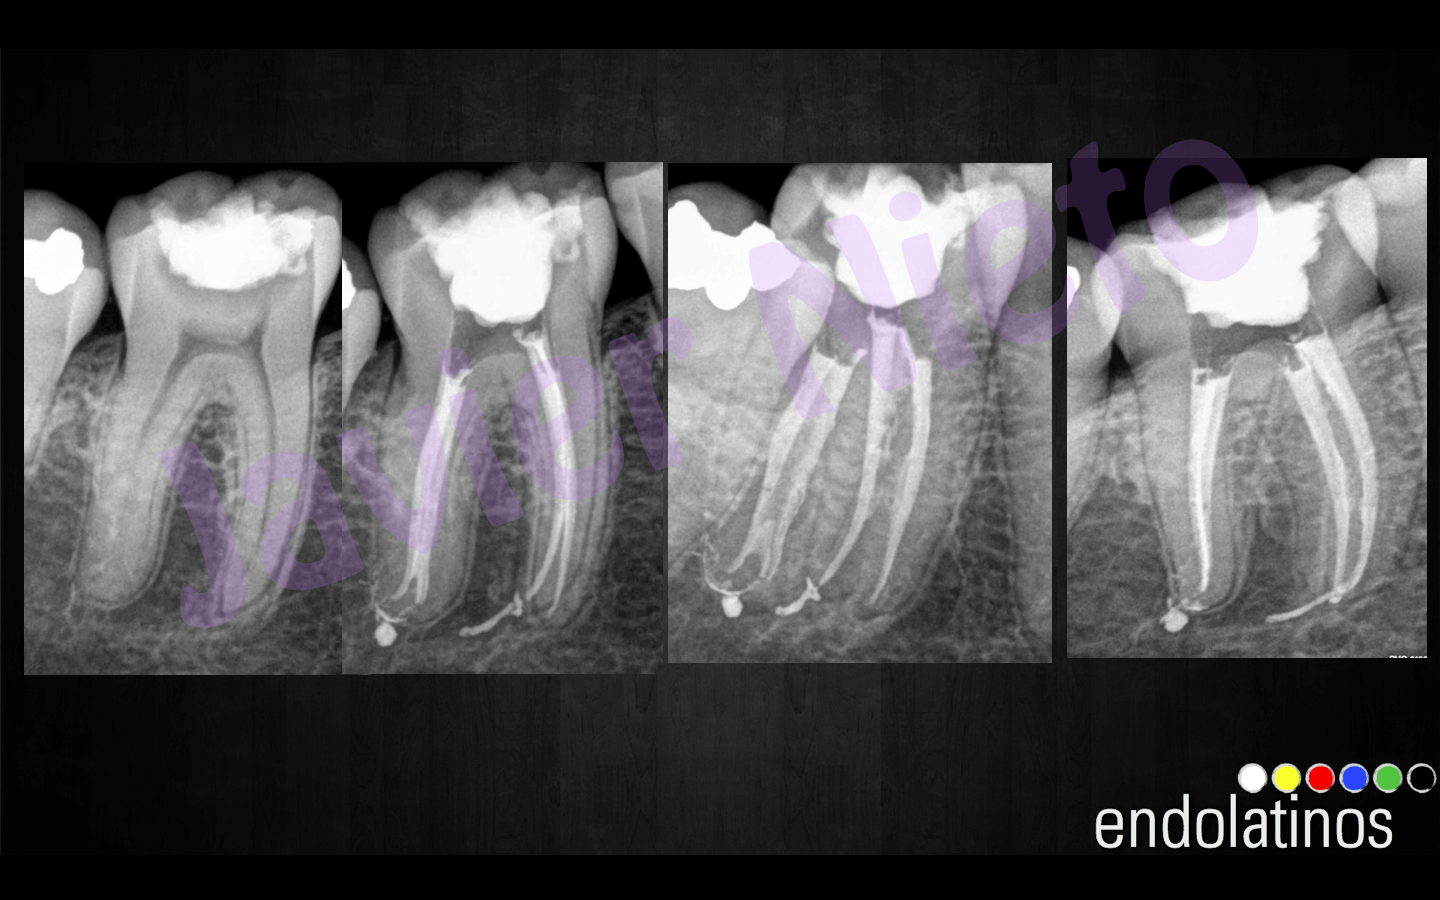

Caso 2:

Estaríamos ante un caso tratado de la misma manera que el anterior, este paciente también sería joven, de unos 28 años de edad, con una pulpitis irreversible, como vemos también presentan itsmos entre los conductos de la raíz MesioVestibular.